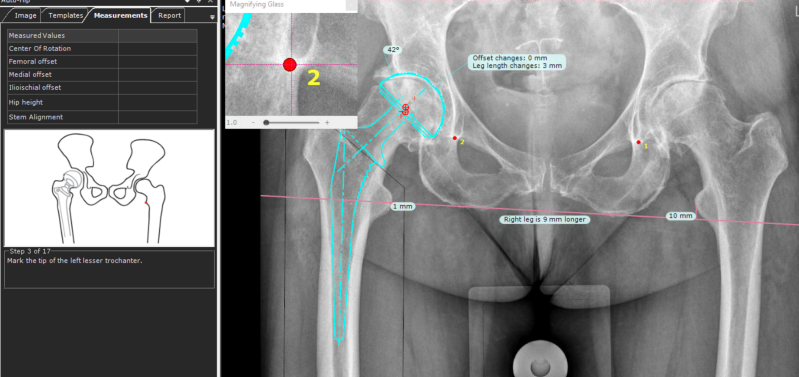

Met een computerprogram (Traumacad - Brainlab) maak ik een werktekening. Het precieze doel van de ingreep hangt af van het type heup, dwz de vormvariant. Je kunt de heup "nabouwen", maar soms op bepaalde punten aanpassen om de spierwerking te verbeteren . Het computer program kan de verschillende opties simuleren vóór de ingreep. Het draaipunt van de heup wordt gepland, dit is belangrijk voor de beenlengte en optimale werking van de spieren met de nieuwe heup. Ook de maten van de nieuwe heup worden bepaald.